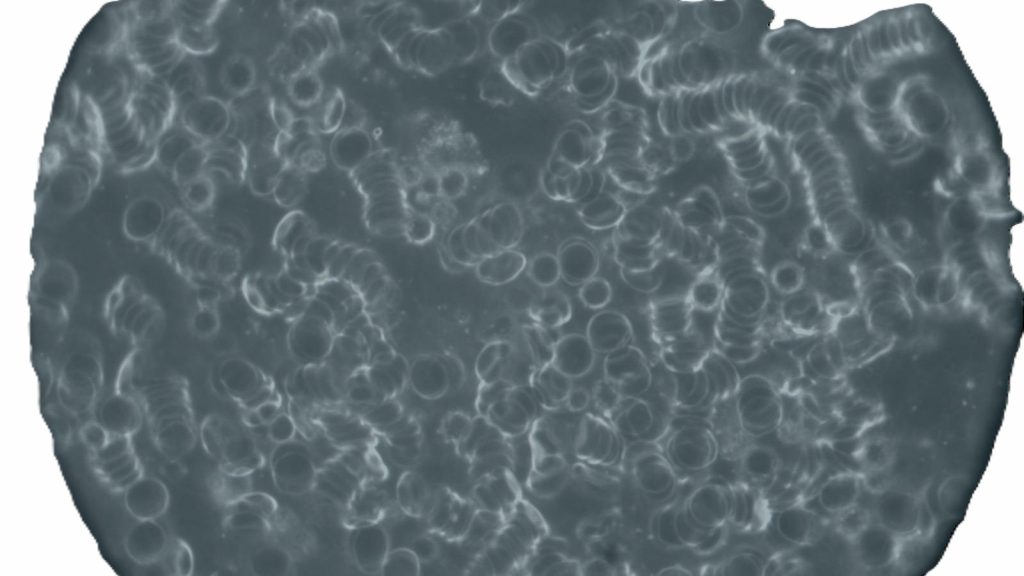

Foto: UV-Licht Mikroskop

Blutbild voll Spikes nach diversen Covidinfektionen und 3x geimpft

Aufgenommen August 2025

Während und nach einer Behandlung mit herkömmlichen Methoden

(Sauerstoff, Nährstoffe, Blutaustausch)

Foto: UV-Licht Mikroskop

Blutbild nach 6 Wochen Behandlung mit Sauerstoff und Nährstoffen

Es sind einzelne Blutzellen erkennbar, es sind allerdings auch weiterhin Spikes im Blut

Aufgenommen Ende Sept. 2025

- Weniger Spikes im Blut

- Einige klar abgesetzte Blutkörperchen

- Keine nachhaltige 100% Ausleitung der Spikes (lineare Tromben)

- Besserung der Sauerstoff / Energieversorgung des Körpers

- Weiterhin zu wenig Sauerstoff im Blut für ein aktives Leben

Foto: UV-Licht Mikroskop

Blutbild 2 Monate nach der Einnahme von ELENANT(R) und einer zusätzlichen Sauerstoffversorgung

Es sind einzelne Blutzellen deutlich erkennbar, es sind keine Spikes im Blut, die Belastung der Zellränder mit Fremdorganismen wird sichtbar

Aufgenommen Ende Dez 2025

Foto: UV-Licht Mikroskop

Blutbild 4 Monate nach der Einnahme von ELENANT(R) und einer zusätzlichen Sauerstoffversorgung

Es sind einzelne Blutzellen deutlich erkennbar, es sind keine Spikes im Blut, der Blick in das klare Bild ermöglicht nunmehr die Besiedlung mir Blutparasiten und Pilzen deutlich zu machen

Aufgenommen Februar 2026